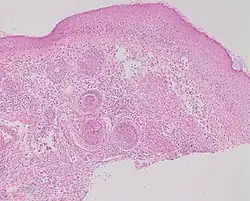

Studies of rosacea and Demodex mites have revealed that some people with rosacea have increased numbers of the mite,[14] especially those with steroid-induced rosacea. Demodex folliculitis (demodicidosis, also known as "mange" in animals) is a condition that may have a "rosacea-like" appearance.[17]

A 2007, National Rosacea Society-funded study demonstrated that Demodex folliculorum mites may be a cause or exacerbating factor in rosacea.[18] The researchers identified Bacillus oleronius as a distinct bacterium associated with Demodex mites. When analyzing blood samples using a peripheral blood mononuclear cell proliferation assay, they discovered that B. oleronius stimulated an immune system response in 79 percent of 22 patients with subtype 2 (papulopustular) rosacea, compared with only 29% of 17 subjects without the disorder. They concluded, "The immune response results in inflammation, as evident in the papules (bumps) and pustules (pimples) of subtype 2 rosacea. This suggests that the B. oleronius bacteria found in the mites could be responsible for the inflammation associated with the condition."[18]